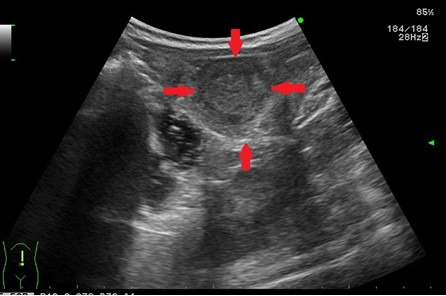

간 관련 질환

- 지방간: 간 조직 내 지방 축적 상태 확인 가능

- 간경화: 간 표면의 거칠음, 크기 변화, 비장 비대 여부 등 확인

- 간암, 간종양: 실질 내부에 덩어리 유무 탐색